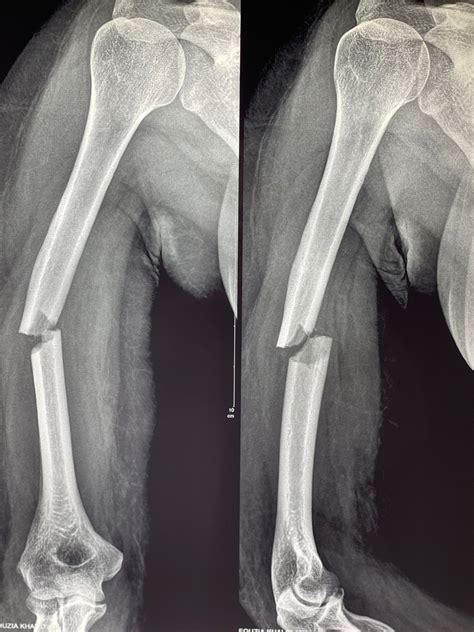

• X-rays: Imaging tests such as X-rays are used to visualize the bone and determine the type and severity of the fracture.

Types of Humerus Bone Breaks

Humerus bone breaks can be classified based on their location and pattern. Common types include:

Type of Fracture Description

Proximal Humerus Fracture Occurs near the shoulder joint, often involving the head or neck of the humerus.

Humeral Shaft Fracture Affects the middle section of the humerus, often due to direct trauma.

Distal Humerus Fracture Occurs near the elbow joint, often involving the condyles or epicondyles.

Supracondylar Fracture A specific type of distal humerus fracture that occurs just above the elbow joint.